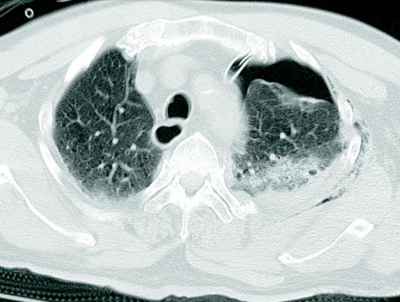

83 歳の男性。作業中に3 mの高さから転落し、背部痛と呼吸困難のため救急車で搬入された。胸腔ドレナージ後の胸部造影 CTを別に示す。

画像所見として認められるのはどれか。3つ選べ。

a. 気胸

b. 肺挫傷

c. 気管断裂

d. 縦隔気腫

e. 肋骨骨折